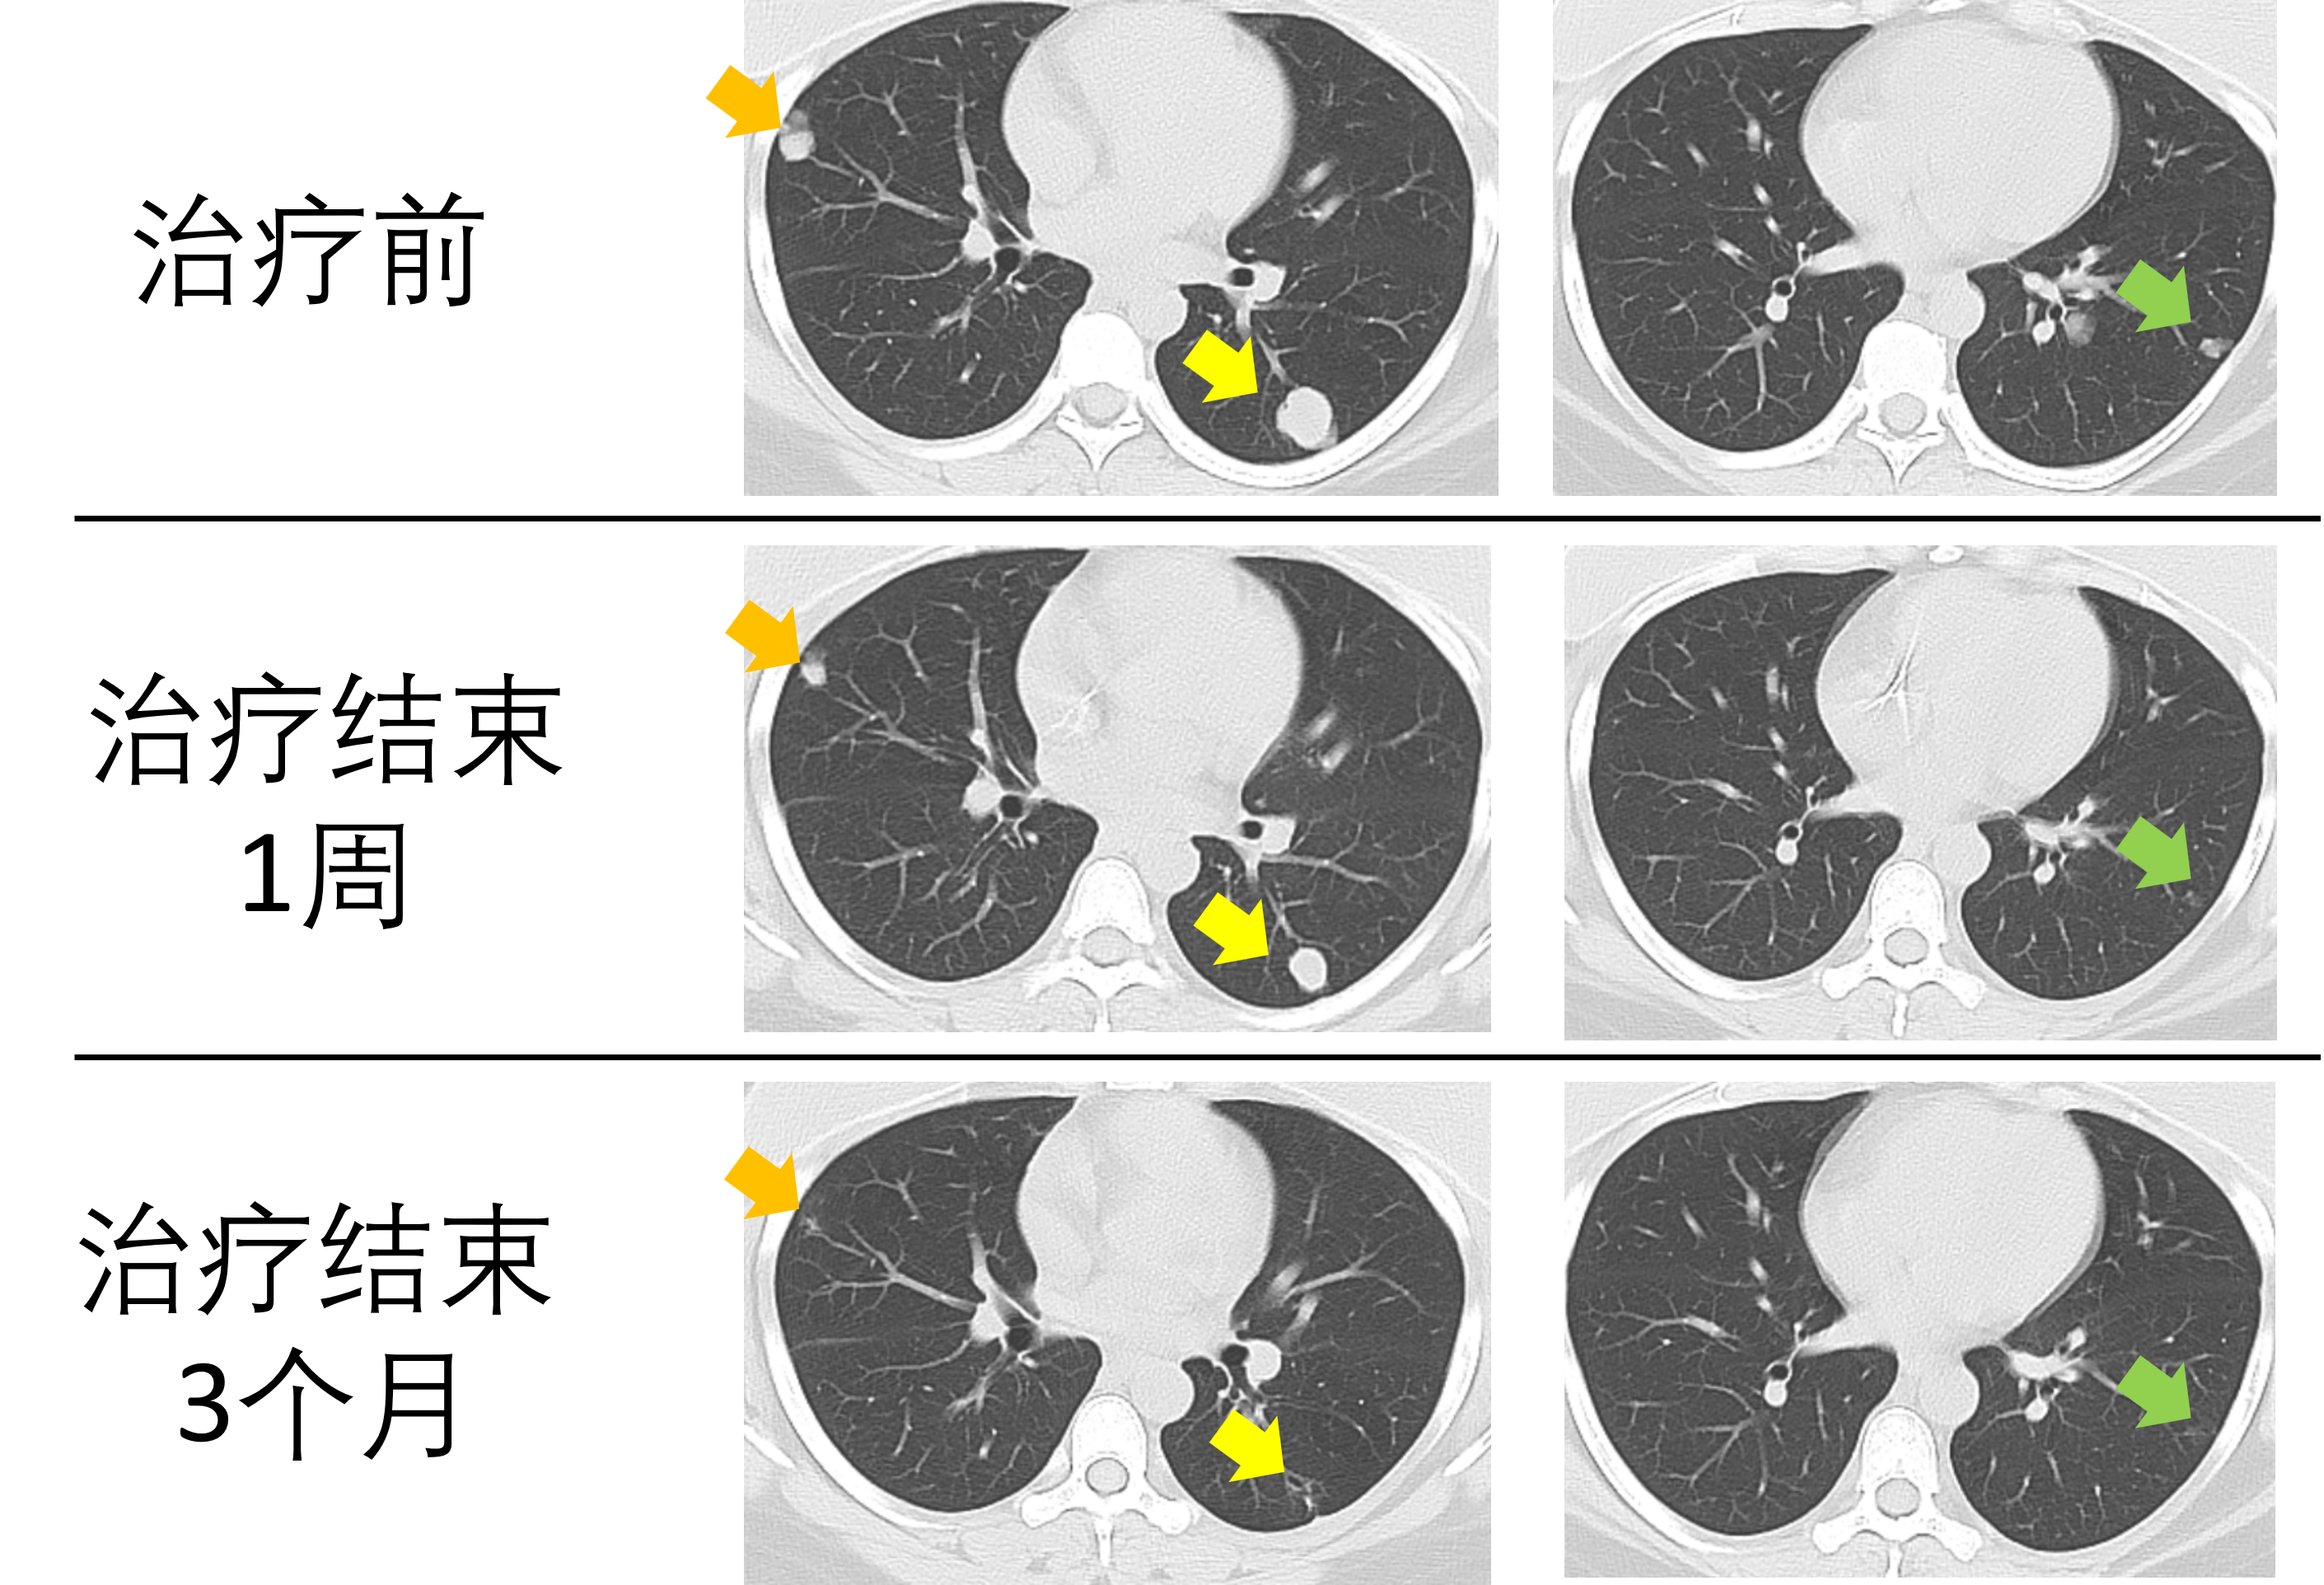

如果有殘留“病灶”的患者全部去做手術(shù)把病灶切除,那么將有至少90%的人“白挨一刀”!考慮到手術(shù)的創(chuàng)傷、風(fēng)險(xiǎn)及其對(duì)肺功能的影響等因素,這樣的手術(shù),誰(shuí)愿意做呢?特別提醒:1.本文所說(shuō)的GTN不包括胎盤部位滋養(yǎng)細(xì)胞腫瘤(PSTT)和上皮樣滋養(yǎng)細(xì)胞腫瘤(ETT)。2.本文的結(jié)論適用于絕大多數(shù)初始治療GTN患者。對(duì)于病情特殊的患者,由于證據(jù)不足,醫(yī)生的個(gè)體化治療意見(jiàn)可能與本文結(jié)論有出入,此時(shí)不可盲目套用本文結(jié)論,而建議與主治醫(yī)師充分溝通,探討利弊。肺轉(zhuǎn)移在妊娠滋養(yǎng)細(xì)胞腫瘤(GTN)中十分常見(jiàn)。不少患者在化療后復(fù)查肺CT的時(shí)候都會(huì)發(fā)現(xiàn)肺部的病灶并未完全消失,而此時(shí)醫(yī)生卻不建議進(jìn)行進(jìn)一步的治療,這是為什么呢?今天我們就來(lái)討論一下這個(gè)問(wèn)題。肺轉(zhuǎn)移是腫瘤細(xì)胞通過(guò)血液循環(huán)到達(dá)肺部的結(jié)果,這種轉(zhuǎn)移途徑醫(yī)學(xué)上稱之為“血行轉(zhuǎn)移”。GTN幾乎是婦科腫瘤中最容易發(fā)生血行轉(zhuǎn)移的腫瘤。而這種特點(diǎn)是由胎盤滋養(yǎng)細(xì)胞的生物學(xué)行為決定的。GTN起源于胎盤的滋養(yǎng)細(xì)胞。眾所周知,胎盤是胎兒從母親血液中獲取營(yíng)養(yǎng)、交換代謝產(chǎn)物的器官。而胎盤的這種功能主要是由滋養(yǎng)細(xì)胞實(shí)現(xiàn)的。在妊娠后,滋養(yǎng)細(xì)胞侵蝕子宮的蛻膜、肌層和動(dòng)脈,進(jìn)而建立胎盤和母體營(yíng)養(yǎng)及代謝產(chǎn)物交換的渠道。這一生物學(xué)行為使得滋養(yǎng)細(xì)胞十分容易進(jìn)入母體的血液循環(huán)。事實(shí)上,在正常孕婦的外周血中,也可以檢測(cè)到滋養(yǎng)細(xì)胞的成分。只不過(guò)在生理性妊娠中,滋養(yǎng)細(xì)胞的生物學(xué)行為是受到精密調(diào)控的,因此這些細(xì)胞即便進(jìn)入母體血液循環(huán)中,也不會(huì)“惹是生非”。而在GTN中,這些細(xì)胞“搖身一變”成為腫瘤細(xì)胞,擁有了更強(qiáng)大的侵蝕和存活能力,因而在子宮以外的部位“定居”并進(jìn)一步“繁衍生息”,此即GTN的轉(zhuǎn)移。肺是GTN最容易發(fā)生轉(zhuǎn)移的部位。肺轉(zhuǎn)移可發(fā)生在約50~70%的GTN病例中,甚至在一些患者中,肺轉(zhuǎn)移灶是唯一的病灶(即包括子宮在內(nèi),其他部位均無(wú)病灶)。在化療結(jié)束后,多達(dá)30-40%的GTN肺轉(zhuǎn)移患者仍可在胸部CT掃描中看到肺部的殘留“病灶”。許多醫(yī)生和患者都會(huì)擔(dān)心殘留“病灶”會(huì)增加疾病復(fù)發(fā)的風(fēng)險(xiǎn)。但是,多項(xiàng)研究均一致地表明,這種肺部殘留“病灶”并不會(huì)增加GTN復(fù)發(fā)的風(fēng)險(xiǎn)。例如,英國(guó)CharingCross滋養(yǎng)細(xì)胞疾病中心回顧分析了99例III期(即有肺轉(zhuǎn)移而無(wú)其他部位轉(zhuǎn)移)GTN患者,其中40.4%的患者在化療結(jié)束6周后的影像學(xué)檢查中發(fā)現(xiàn)肺部有殘留“病灶”。在治療結(jié)束5年后的隨訪中,絕大多數(shù)患者都未出現(xiàn)疾病復(fù)發(fā),且有殘留“病灶”和沒(méi)有殘留“病灶”的患者的復(fù)發(fā)率無(wú)明顯差異(5年無(wú)復(fù)發(fā)生存率:有殘留“病灶”者為91.2%,無(wú)殘留“病灶”者為94.9%)。這里再為大家提供一個(gè)數(shù)字:98%的GTN復(fù)發(fā)發(fā)生在治療結(jié)束后的5年內(nèi),因此如果治療結(jié)束后5年內(nèi)未出現(xiàn)疾病復(fù)發(fā),在接下來(lái)的時(shí)間中復(fù)發(fā)的幾率更是微乎其微。如果說(shuō)上面的內(nèi)容專業(yè)術(shù)語(yǔ)較多、難以理解,那么接下來(lái)我用更加通俗的語(yǔ)言“翻譯”一下:GTN患者治療后,不管肺部有沒(méi)有殘留“病灶”,復(fù)發(fā)率都沒(méi)有顯著差別。即便肺部有殘留“病灶”,復(fù)發(fā)率也不超過(guò)10%。那么在這樣的前提下,我們做一個(gè)極端的假設(shè):假如手術(shù)切除殘留“病灶”能夠達(dá)到預(yù)防復(fù)發(fā)的目的,那么從手術(shù)中獲益的患者比例是多少呢?最多10%!也就是說(shuō),如果有殘留“病灶”的患者全部去做手術(shù)把病灶切除,那么將有至少90%的人“白挨一刀”!考慮到手術(shù)的創(chuàng)傷、風(fēng)險(xiǎn)及其對(duì)肺功能的影響等因素,這樣的手術(shù),誰(shuí)愿意做呢?接下來(lái),我們進(jìn)一步來(lái)探討下一個(gè)問(wèn)題:對(duì)于肺部有殘留“病灶”、并且復(fù)發(fā)的患者而言,手術(shù)切除殘留“病灶”能有效預(yù)防復(fù)發(fā)嗎?答案是不能!有研究提示,部分患者在治療后手術(shù)切除了殘留“病灶”,僅有少數(shù)患者的病理證實(shí)“病灶”中仍有活性腫瘤細(xì)胞。而術(shù)后,不論病理檢查是否發(fā)現(xiàn)了活性腫瘤細(xì)胞,都有一定比例的患者復(fù)發(fā)。因此,從預(yù)防復(fù)發(fā)的角度講,目前沒(méi)有確切的證據(jù)支持手術(shù)切除殘留“病灶”能夠降低GTN的復(fù)發(fā)風(fēng)險(xiǎn)。那么,我們應(yīng)該如何對(duì)待肺部的殘留“病灶”呢?答案是隨訪。隨訪的內(nèi)容主要有兩方面。其一是血hCG的監(jiān)測(cè),因?yàn)閔CG升高是診斷GTN復(fù)發(fā)的必要條件(注:PSTT和ETT除外)。其二是定期復(fù)查影像學(xué)檢查。在化療后的隨訪中,大多數(shù)患者的肺部殘留“病灶”會(huì)逐漸縮?。▓D1),部分患者的殘留“病灶”大小無(wú)明顯變化。然而,不論何種情況,病灶增大是很罕見(jiàn)的。如果一位患者的肺部殘留“病灶”增大而血hCG正常,我們就要警惕這個(gè)病灶是否是其他疾?。ㄈ绺腥净蚍卧l(fā)腫瘤)導(dǎo)致的。此時(shí)我們可能需要進(jìn)一步檢查加以鑒別。寫在最后的碎碎念:前面論述的是大多數(shù)GTN患者治療結(jié)束后,如血hCG水平正常,無(wú)需對(duì)肺殘留“病灶”做進(jìn)一步治療。但對(duì)于特殊患者而言(如復(fù)發(fā)風(fēng)險(xiǎn)較高的患者),目前尚無(wú)充分的證據(jù)指導(dǎo)治療,因此這些患者可能更加需要個(gè)體化的治療。這種情況下,應(yīng)該具體問(wèn)題具體分析,萬(wàn)不可盲目套用本文的結(jié)論。此外,我在臨床上也遇到過(guò)個(gè)別GTN合并肺癌的患者。盡管十分罕見(jiàn),但如果臨床醫(yī)生懷疑肺部結(jié)節(jié)的性質(zhì),必要的時(shí)候還是應(yīng)該進(jìn)一步診治的。參考文獻(xiàn):1.PowlesT,SavageP,ShortD,YoungA,PappinC,SecklMJ.Residuallunglesionsaftercompletionofchemotherapyforgestationaltrophoblasticneoplasia:shouldweoperate?BrJCancer.2006Jan16;94(1):51-4.doi:10.1038/sj.bjc.6602899.PMID:16404359;PMCID:PMC2361065.2.Bouchard-FortierG,GhoraniE,ShortD,AguiarX,HarveyR,UnsworthN,KaurB,SarwarN,SecklMJ.Followingchemotherapyforgestationaltrophoblasticneoplasia,doresiduallunglesionsincreasetheriskofrelapse?GynecolOncol.2020Sep;158(3):698-701.doi:10.1016/j.ygyno.2020.06.483.Epub2020Jul9.PMID:32654764.3.LiX,YangB,ChenJ,ZhangY,SunQ,AiJ,LiK.DotheResidualLungLesionsThreatenGestationalTrophoblasticNeoplasiaPatients?IntJGynecolCancer.2018Sep;28(7):1410-1417.doi:10.1097/IGC.0000000000001311.PMID:30142125.4.WangW,KongY,LiY,WanX,FengF,RenT,ZhaoJ,XiangY,YangJ.Pulmonaryresectionofresiduallesionsofpulmonarymetastasisfromgestationaltrophoblasticneoplasia.IntJGynecolCancer.2023Sep4;33(9):1376-1382.doi:10.1136/ijgc-2023-004375.PMID:37524495;PMCID:PMC10511965.